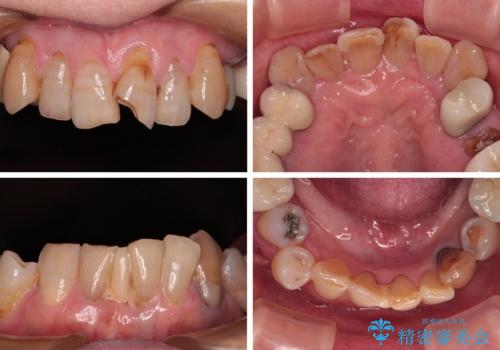

- 長年気にしていた捻れた前歯が欠けたとのことで来院された患者様です。

矯正治療に抵抗があったそうですが、前歯が欠けたことをきっかけに、矯正治療で歯列を整えた上で、セラミッククラウン治療を行う決心が付いたとのことでした。

デコボコが強いため、ブリッジや残根となっている部分のスペースを利用して歯列を整え、変色や欠けている歯をオールセラミッククラウンによる補綴治療を行うこととしました。

歯肉移植などによる前歯部の歯肉ライン改善を提案しましたが、口を開けたときにほとんど見えないので気にならないとのことで、特に処置を行うことなく補綴治療を行いました。